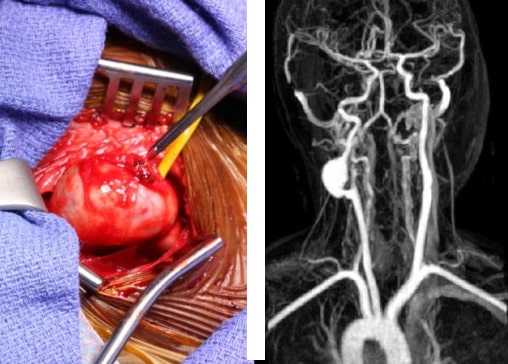

Пример аневризмы внутренней сонной артерии верхушки пирамиды височной кости

Женщина 46 лет была направлена общим оториноларингологом для осмотра по поводу «подозрительного образования» на КТ. У пациентки имеется хронический средний отит слева, в 2005 и 2006 годах ей выполнялись операции на левом ухе. На настоящий момент в ухе сформирована полость после мастоидэктоми с разрушением задней стенки (открытого типа). Пациентка жаловалась на шум в ухе и короткие эпизоды головокружения (не истинного вертиго). Других примечательных жалоб со стороны ушей не было.

На КТ без контрастирования от 16 июня 2008 года определялись послеоперационные изменения, соответствующие открытой мастоидэктомии с тимпанопластикой слева, а также экспансивное образование в нижней части верхушки пирамиды левой височной кости. Образование вызывало ремоделирование окружающей кости, максимальный размер составлял 13 мм. Изменения были характерны для аневризмы внутренней сонной артерии.

Далее были выполнены МРТ с гадолинием и МР-ангиография (МРА), результаты интерпретировались с учетом данных КТ. Оказалось, что образование в левой височной кости не является частью внутренней сонной артерии. Оно было гиперинтенсивным на изображениях в режиме Т1, и гетерогенным в режиме Т2. Данные изменения соответствовали холестериновой гранулеме. Учитывая отсутствие симптоматики, было принято решение о выжидательной тактике.

б - Магнитно-резонансная ангиография головного мозга. Образование в левой височной кости не является частью внутренней сонной артерии. КТ левой височной кости в (а) аксиальной и (б) фронтальной проекциях,

на которой определяется экспансивное образование верхушки пирамиды. а - МРТ в (а) фронтальной и (б) аксиальной проекциях. Гиперинтенсивное образование в нижней части верхушки пирамиды левой височной кости.

б - МРТ в (а) фронтальной и (б) аксиальной проекциях. Гетерогенное образование верхушки пирамиды левой височной кости.